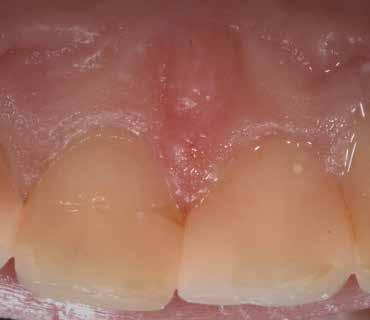

A korai harmicas éveiben járó hölgy rendelőnkbe érkezésének oka a jobb felső nagymetsző fog bizonytalan érzkenysége, elmondása alapján gyermekkorában trauma érte a felső frontrégiót. A frakturált klinikai koronákat kompozittöméssel helyreállították, egyéb kezelést akkor nem tartottak szükségesnek. Az utóbbi hónapokban tapasztalt érzékenység miatt kereste fel rendelőnket. A klinikai vizsgálat (1. és 2. kép) és a CBCT felvétel (3. kép) alapján diagnosztizált külső gyökérreszorpció megoldására a fog eltávolítását, implantátum

bukkális 1. kép: Kiindulási állapot, 2020. január. 3. kép: Kiindulási CBCT felvétel. 2. kép: Kiindulási állapot a palatinális oldal felől.